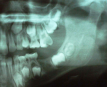

Molar migrations after loss of first molars, 8-year history: 1999

Figure 28

Molar migrations after loss of first molars, 8-year history: 2003

Figure 29

Molar migrations after loss of first molars, 8-year history: 2007

Figure 30

In 1998, a 7-year-old boy was brought in for emergency care with the chief complaint of toothache of the mandibular left permanent first molar. The malformed tooth was non-restorable and extracted, with no other treatment options. The child was not returned for continuing routine care but was returned on an emergency basis in 1999. He had a dentoalveolar abscess of the severely carious maxillary left permanent first molar, and the tooth was judged non-restorable (Figure 28). That molar was extracted. The patient was not returned to the office again until 4 years later, in 2003. The maxillary second molar had migrated into good position distal to the second premolar, and the third molar followed into place (Figure 29). The mandibular second molar was tipped mesially, followed by the crown of the third molar. Four years after that (2007), the patient returned as a 15-year-old. The second and third molars had migrated into position, with no orthodontic intervention (Figure 30).